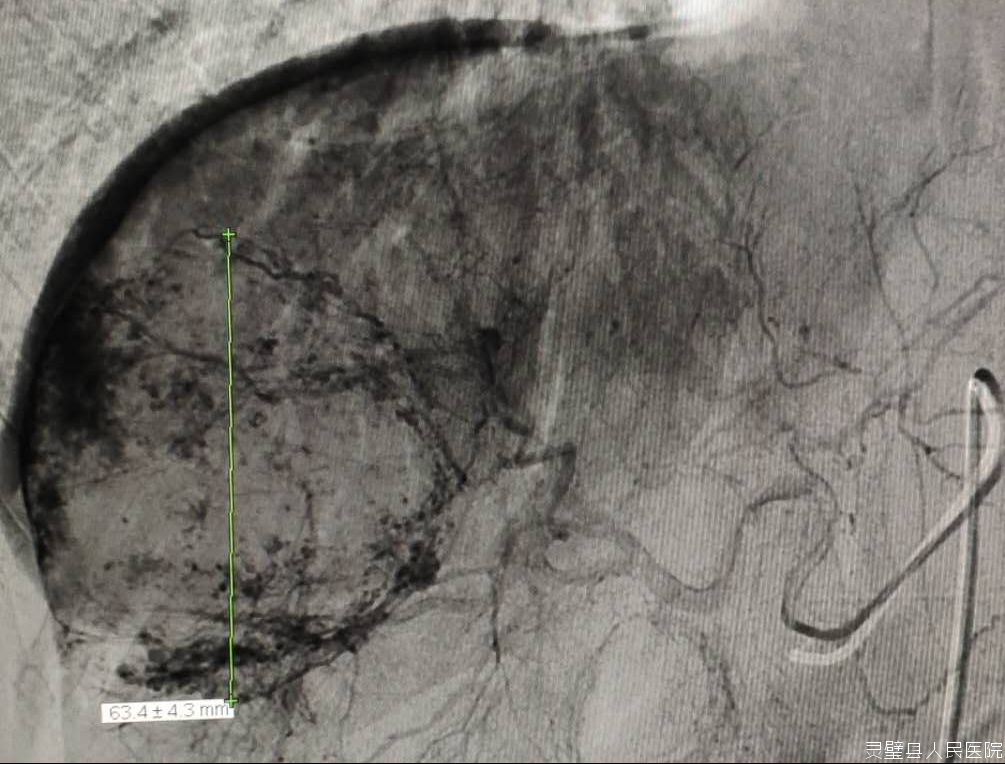

通过股动脉插管将造影剂注入肝动脉了解病变大小,将抗癌药物、栓塞剂注入肝动脉进行区域性的局部化疗治疗。介入治疗局部药物浓度较全身化疗高达数十倍,而且阻断肿瘤血供,因此双管齐下疗效好、毒性小。

目前肿瘤外科在介入治疗方面已常规开展:1.肝脏疾病的血管内介入治疗技术:肝动脉化疗栓塞术、肝动脉栓塞术,包块肝血管瘤、肝脏局灶性结节增生、肝腺瘤等;肝动脉灌注化疗术:肝癌肝动脉灌注化疗。2.肝脏疾病的非血管介入治疗技术:肝癌、胆管癌、胰腺癌、十二指肠癌等造成的梗阻性黄疸经皮穿刺胆道引流术、经皮穿刺胆囊引流术,肝脓肿穿刺引流术、肝囊肿穿刺引流硬化术。3.食管癌狭窄的支架植入术。4.下肢深静脉血栓的髂总静脉滤器植入等。